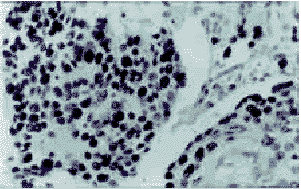

图2 食管浸润癌组织中p53蛋白的表达

图3 食管浸润癌间质中PCNA的表达

38例p53表达阳性的病例中,只有15例IgG表达(39.47%),而p53阴性的42例中,IgG阳性表达的高达30例(71.43%),两者之间有显著性差异(P<0.05)。同样,PCNA阳性的病例中,IgG阳性表达的只占39.02%,而PCNA阴性的病例中,IgG阳性表达的细胞高达74.30%(图1,2,3)(表2)。

1.3.2 S-P免疫组化染色法主要步骤:0.3%甲醇过氧化氢阻断内源性过氧化物酶,滴加p53、PCNA单克隆抗体,4℃湿盒内过夜,滴加生物素化二抗孵育,滴加稀释的辣根过氧化物酶标记的链霉卵白素。上述各步均以PBS冲洗3次。DAB显色复染。